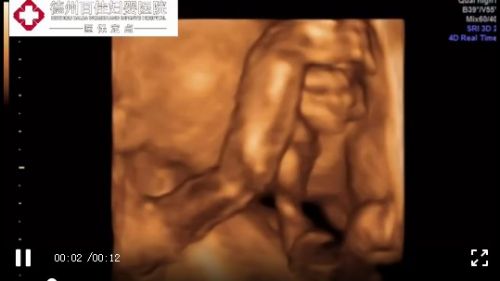

的确,超声影像(四维彩超),也就是胎儿系统超声检查能不能顺利过关,除了跟宝妈自身情况有关之外,还与宝宝的配合程度有很大的关系。

这一点,相信那些做过胎儿系统超声检查的孕妈妈都深有体会,有时候宝宝不是很配合,会拿小手遮住脸部或者完全背对着你,那孕妈们可就“痛苦”了……有时候甚至一上午折腾了两三次也未必有效,孕妈们也是欲哭无泪……